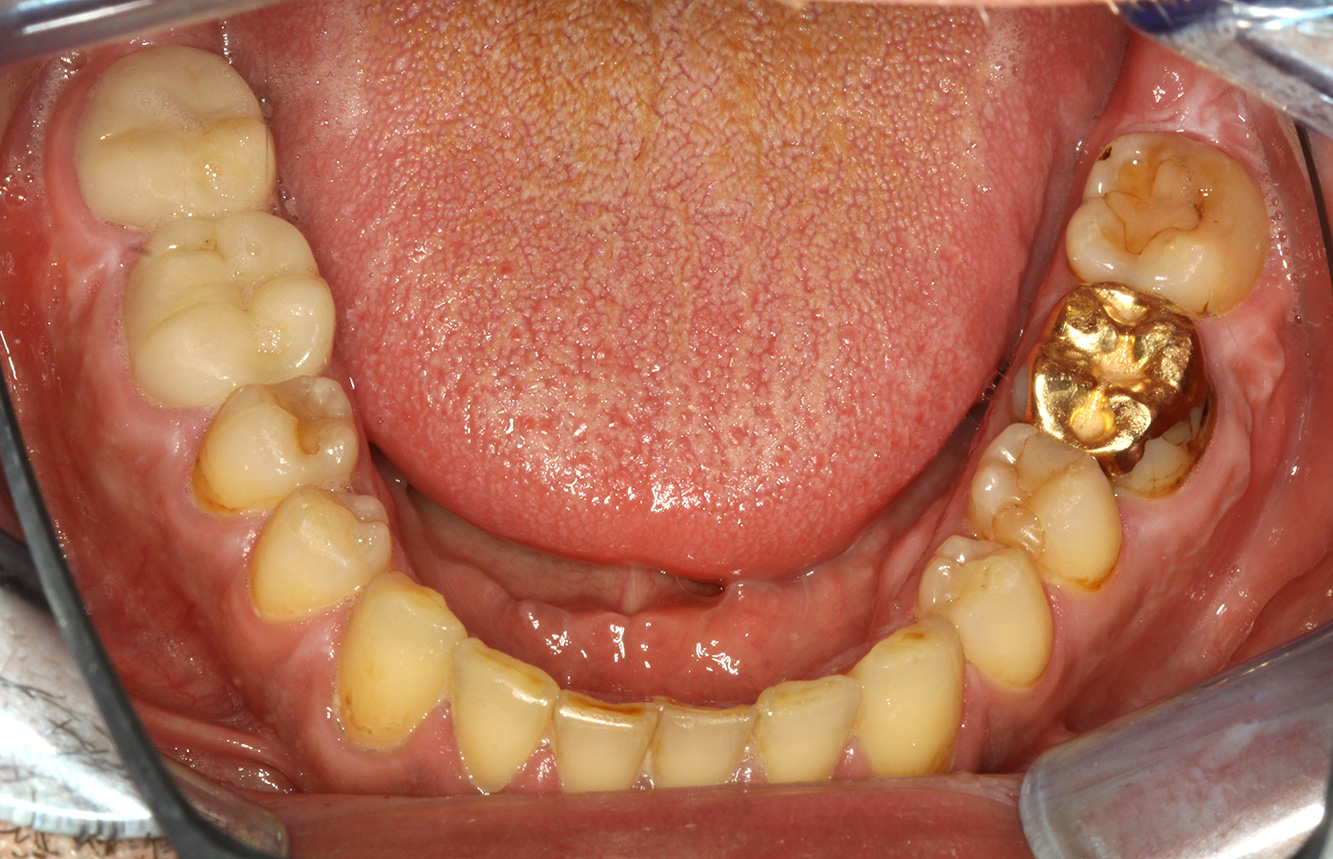

Der Patient ist 39 Jahre mit Z.n. Herzklappenersatz wegen Klappenfehlers und Endokarditis. Als Antikoagulans (Gerinnungshemmer) wird regelmäßig ASS 100 eingenommen. Aus dem Bereich Lebensstil ist die Ernährungsweise als kariesfördernd einzustufen, da mit hoher Regelmäßigkeit zuckerhaltige Lebensmittel sowie sechs bis sieben Mahlzeiten täglich verzehrt werden. Die Mundgesundheit des Patienten zeigt ein mittleres Kariesrisiko mit aktiven Läsionen. Das Parodontitisrisiko ist niedrig, es besteht eine Gingivitis. Es ergeben sich folgende Empfehlungen für die Prophylaxebehandlung.

Für die Prophylaxesitzung lassen sich keine spezifischen Instrumentierungsempfehlungen ableiten. Durch den gezielten Einsatz von Pulverstrahl und rotierend Polieren können Plaque und Verfärbungen an den Restaurationsrändern schonend entfernt und Wiederbesiedlungsnischen für kariogene Bakterien reduziert werden (20).

Zur weiteren Unterstützung der Kariesprävention ist eine Fluoridierung, besonders um der Neuentstehung im Bereich der Restaurationsränder vorzubeugen, und eine Versiegelung der Wurzeloberflächen empfehlenswert. Beide Maßnahmen können die angegebene Temperatursensibilität der Zähne reduzieren.